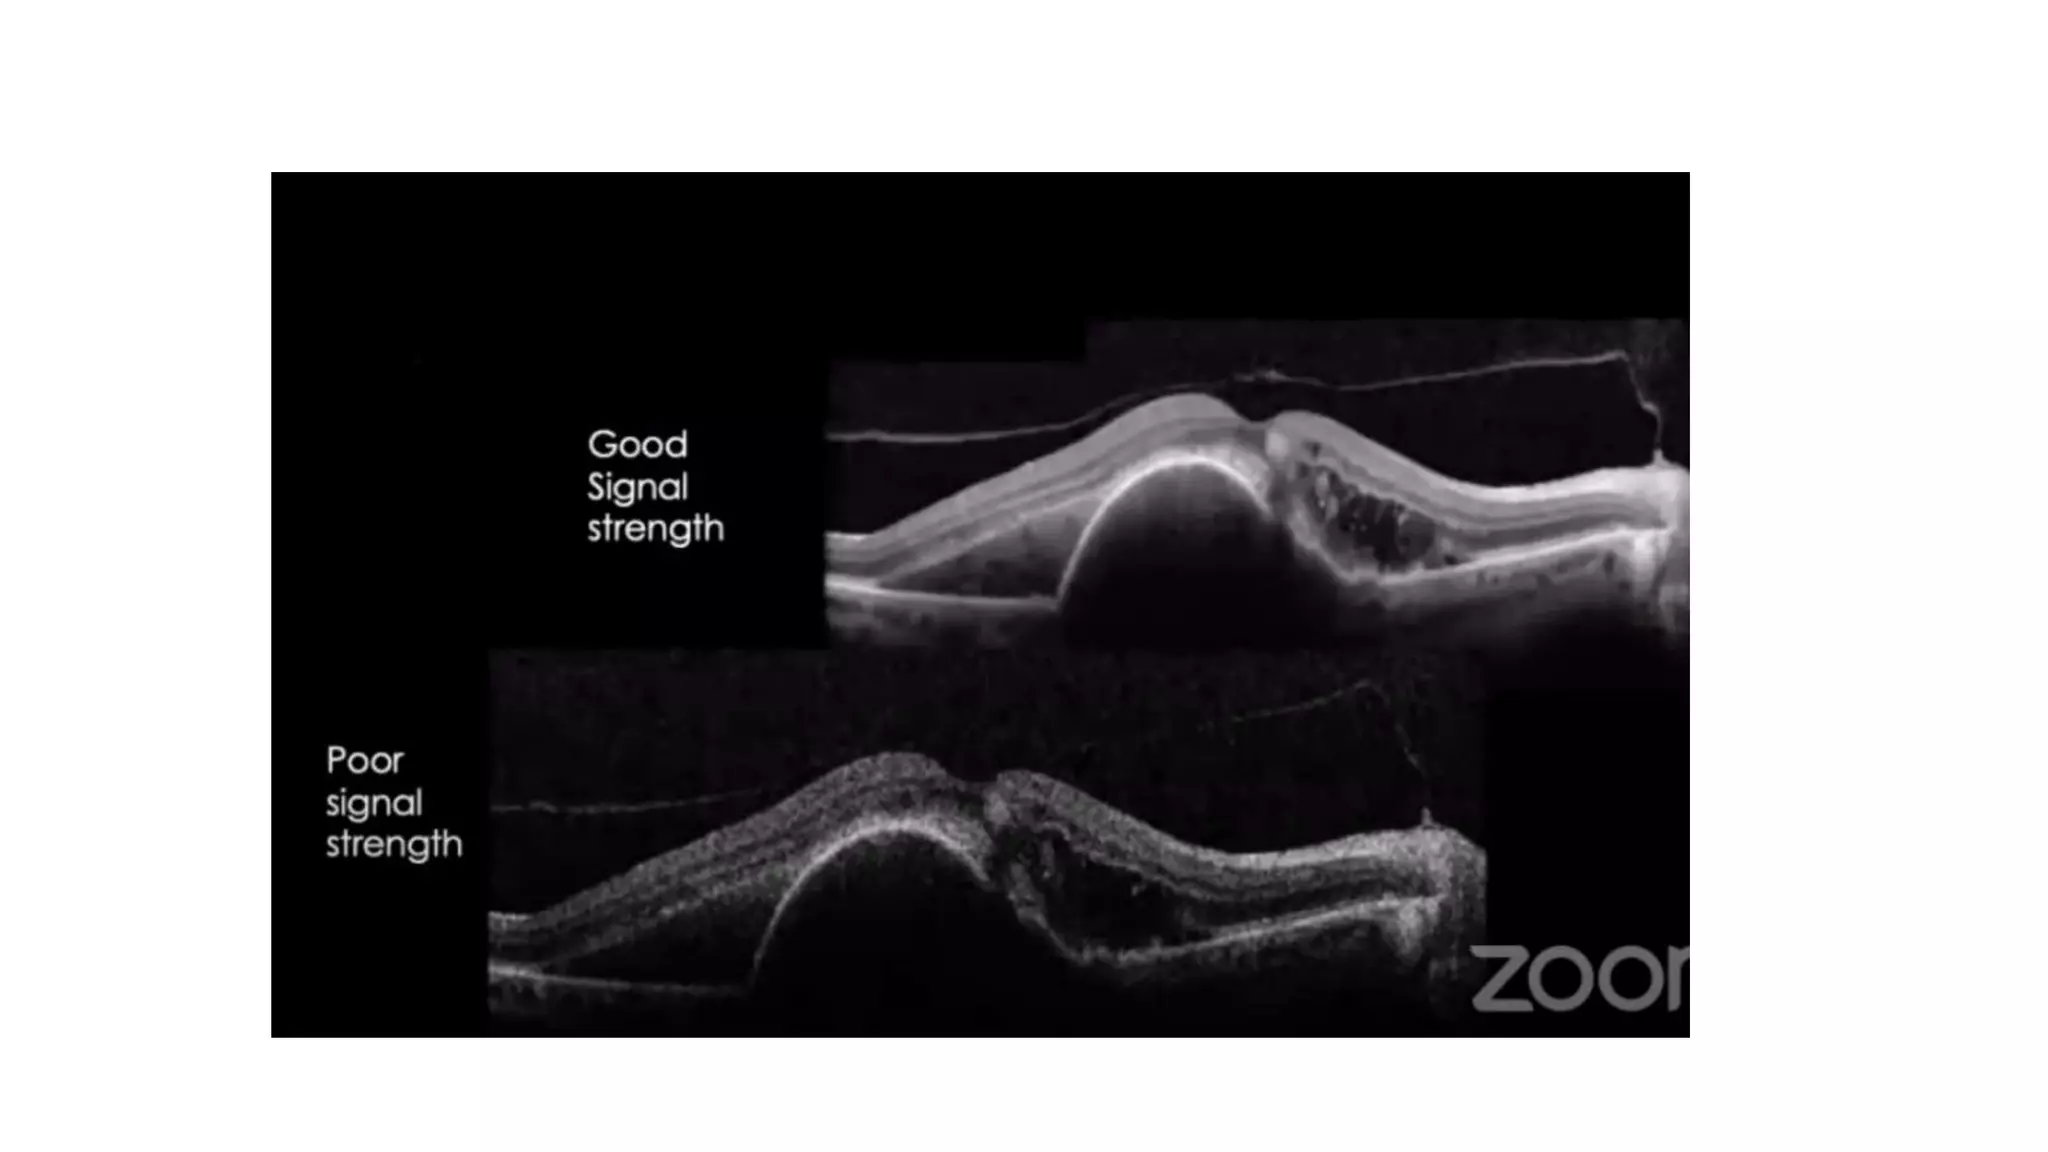

Signal Strength

• Signal strengths of ten are most desirable.

• A strength of six or higher are acceptable.

• If the signal strength is less than ten, you should save and then repeat the scan as

the one you saved may be the best scan of all future scan

There are threeimportant parameters that can affect the interpretation of a scan. They are signal strength, centration, and scan alignment

• 82.

Complications that candecrease signal strength : 1. Poor Fixation or disease that can prevent fixation 2. Lack of patient cooperation 3. Dry Eye 4. Corneal opacity 5. Cataract 6. Vitreous opacities i.e., silicone oil, blood, floaters, and asteroid hyalosis. 7. Blinking Signal Strength

• 83.

Signal strength • Signalstrengths of ten are most desirable. • A strength of six or higher are acceptable. • If the signal strength is less than ten, you should save and then repeat the scan as the one you saved may be the best scan of all future scan Problem?

• 84.